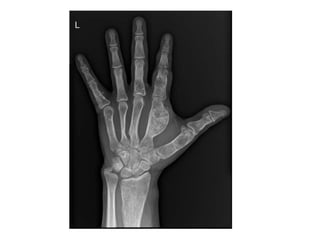

• The commonest location is the tubular bones of the hand,

followed by the femur and humerus.

• Radiographically, the lesion is most commonly central with

rounded, well-defined, lobulated edges and a thin rind of

reactive sclerosis.

• It contains glandular, popcorn, ring-like opacities.

• They can reach considerable size but rarely exceed 6 cm.

• MRI demonstrates the black signal voids of internal

calcification and isotope bone scan is hot in most lesions.

• Histologically, the lesion contains lobules of cartilage

with areas of calcification.

• The chondrocytes are usually sparse with small, round,

dense nuclei.

• if there is evidence of chondroma permeating within

the marrow spaces and haversian system, this is highly

suggestive of chondrosarcoma.

• Treatment is usually not required although,

occasionally in the hand, the lesion may be removed

through curettage, particularly if there is pain or

pathological fracture.

• Serial X-rays may be helpful if there is a suspicion of a

grade 1 chondrosarcoma, as enchondromas in skeletal

maturity do not grow.

• On X-ray, the chondromas can be very large with

consequent expansion of the bone, thinning of

the cortex or, indeed, no cortex at all (Figure 9.14).

• In Maffucci syndrome, the presence of haemangioma

may be seen on imaging by phleboliths.

• Histologically, the chondromas appear more cellular

than solitary chondromas, with more proliferative

potential.

• Transformation to a secondary sarcoma is seen in both

these conditions.

• In Ollier’s disease, this may occur in 20–30% of

patients; in Maffucci syndrome, this is much more

common and is likely to be greater than 50%.